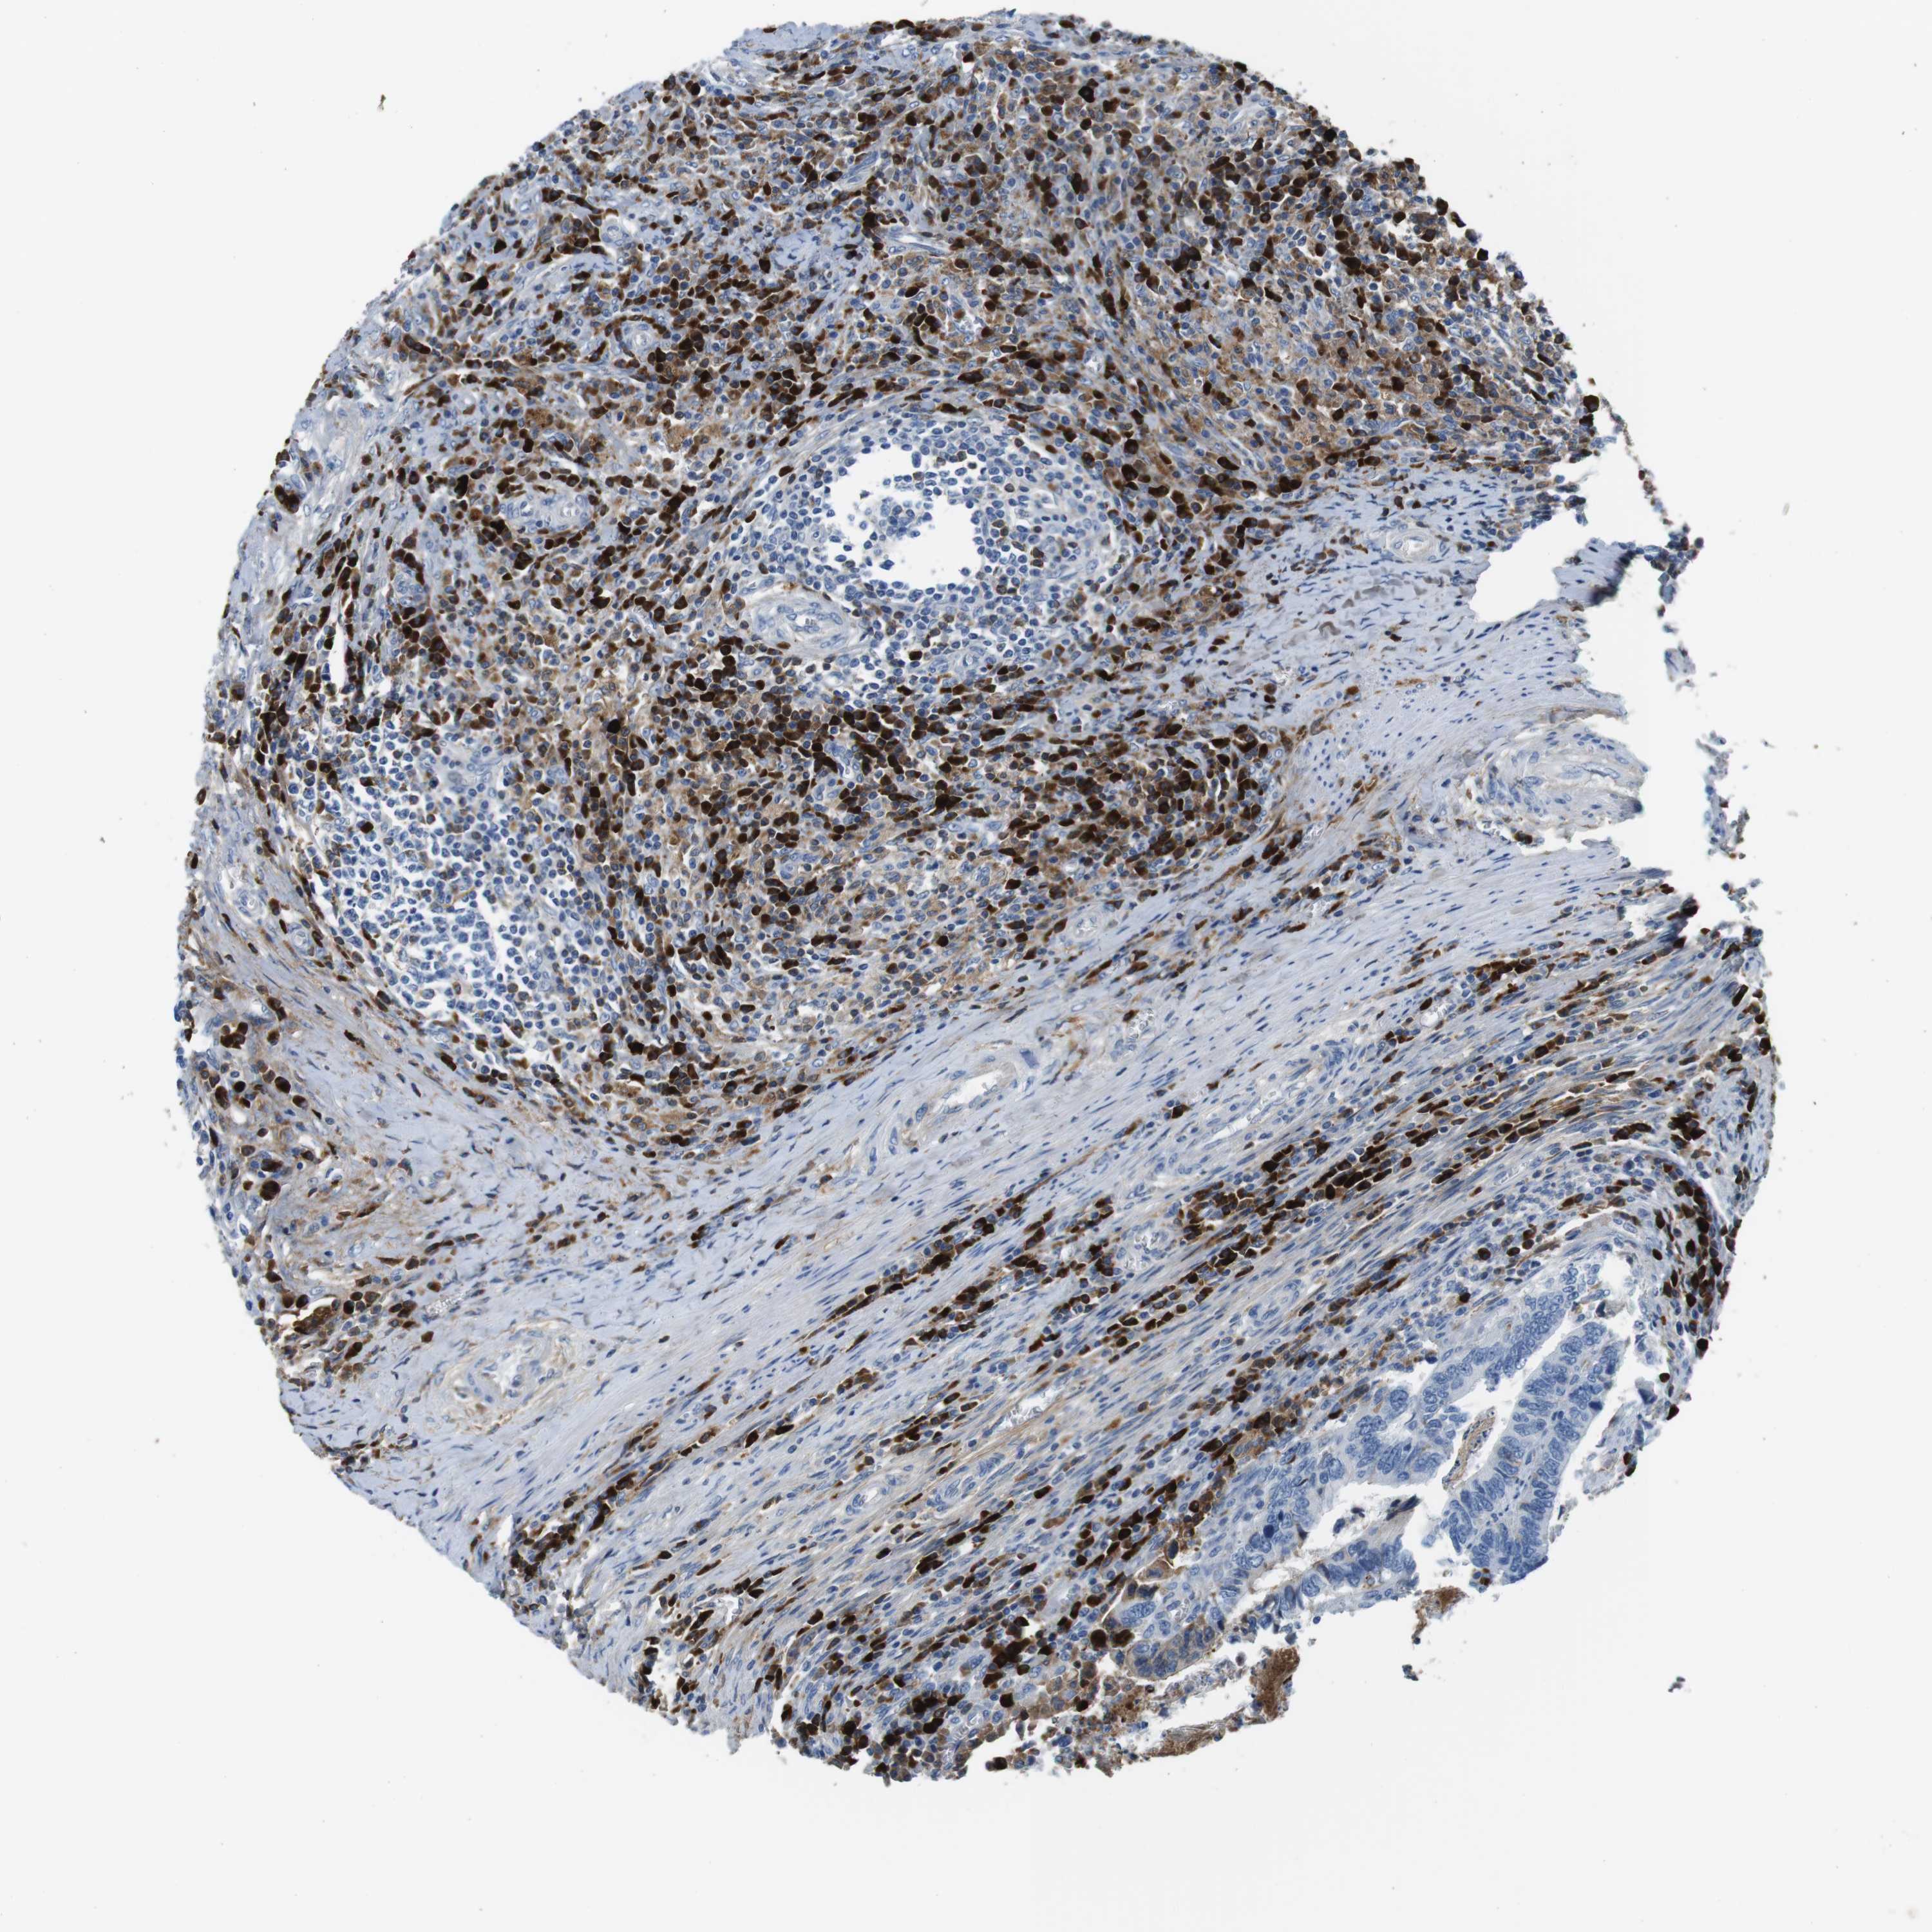

CANCER COLORECTAL CANCER Show tissue menu

Colorectal cancer

Human cancer

Colon adenocarcinoma